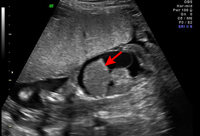

Hidropesía fetal con ascitis y hepatomegalia (flecha) diagnosticadas mediante ultrasonido prenatal

Ottawa Hospital; utilizado con el consentimiento de la paciente